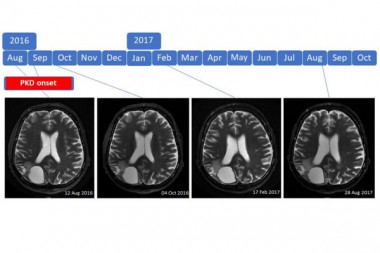

Introduction: Prognosis for patients with high-grade brain tumor is poor and survival did neither substantially change with advances in chemotherapy, radiotherapy and molecular profiling. Ketogenic diets have been suggested as a promising alternative therapy.